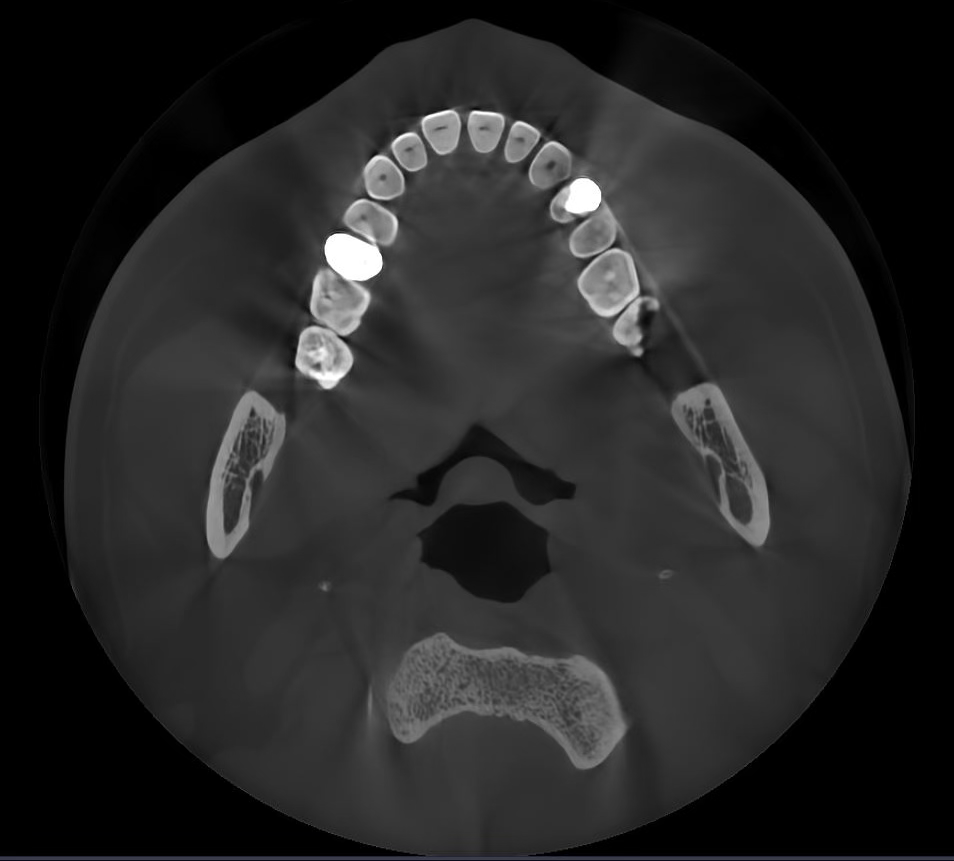

La tecnología IA

Borra los artefactos metálicos y restaura con precisión las estructuras dentales, las coronas metálicas y los implantes basados en principios matemáticos.